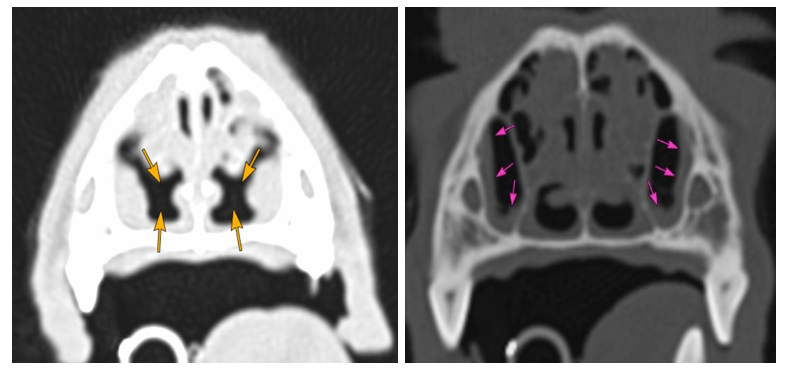

Imagen derecha: Mucosa de senos maxilares moderadamente engrosada (flechas rosas)